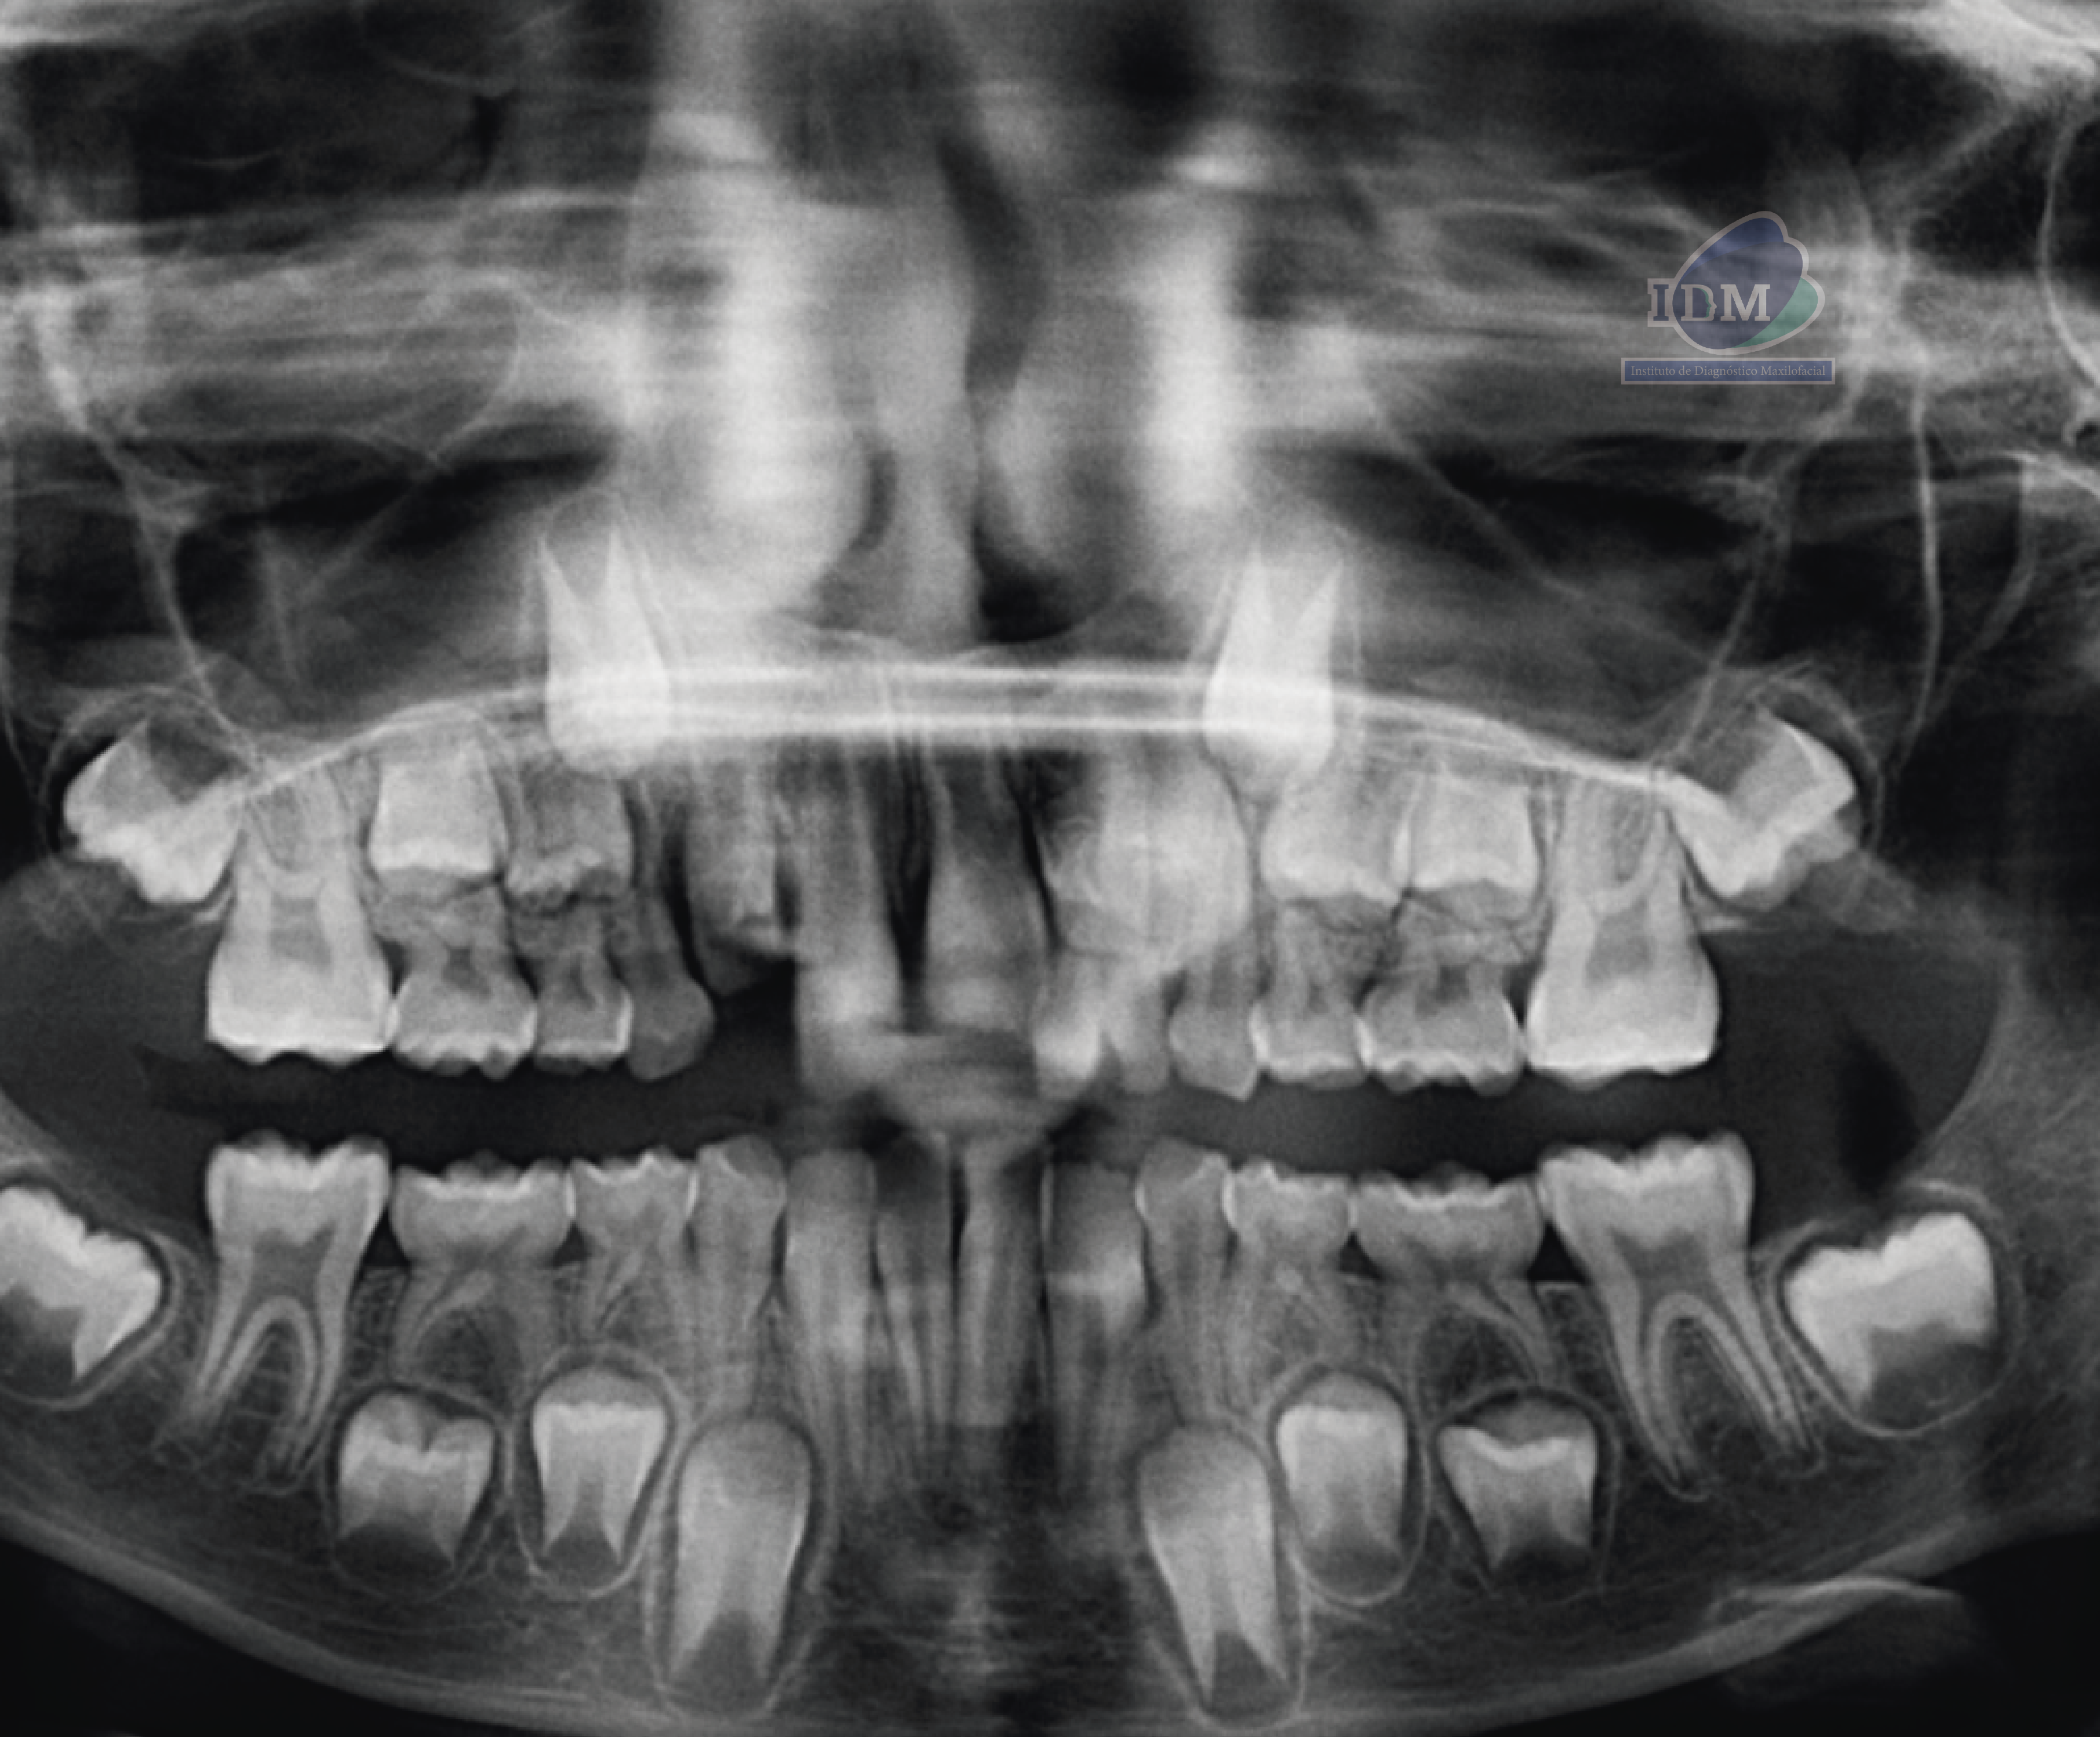

En la radiografía panorámica (Figura 1), se observa pieza supernumeraria en evolución intraósea ubicada entre la piezas 22 y 23, además de una alteración en la morfologia coronaria de pieza 22.

Además se observa la persistencia de piezas deciduas 61 y 62.

Radiografia Panorámica